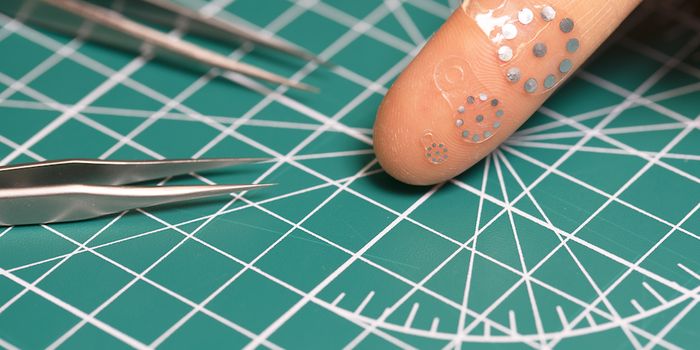

AUG 31, 2024TechnologyA team of researchers at the California Institute of Technology have released a prototype for a new type of advanced, sm ...

AUG 24, 2024TechnologyA team of researchers at the Faculty of Medicine and University Hospital Cologne, in the University of Cologne, have des ...